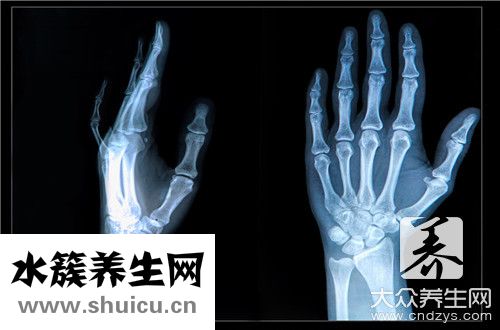

骨折愈合是一個連續不斷的過程。一般來說可分為三期。第一期稱為血腫機化期。骨折后6-8小時內血腫開始形成凝血塊,毛細血管增生,各種纖維細胞侵入,血腫發生機化,肉芽組織變為纖維結締組織,使骨折斷端初步連接在一起,這一時期約在骨折后2-3周完成。

第二期稱為原始骨痂形成期。骨折斷端的纖維結締組織,經過軟骨細胞的增生、變性、鈣化而骨化,這是軟骨內骨化,這一時期一般需要4-8周。第三期稱為骨痂改造期。原始骨痂進行改造,成骨細胞增生,新生骨小梁也逐步增加,并逐漸排列成規則致密的骨小梁,使骨折斷端形成骨性連接,這一時期需要8-12周。這樣從骨折開始到骨性連接一般需要三個月左右的時間。所以說,傷筋動骨一百天是有一定的道理的。

但是骨折愈合過程受到許多因素的影響,如:年齡、身體健康情況、骨折部位、骨折類型、軟組織損傷程度、是否感染及治療方法等。如小兒股骨骨折一個月左右就基本愈合,成年人往往需要3個月后才能愈合。血液循環豐富部位骨折愈合快,血液循環供應差的部位就愈合慢。骨折對位不良,軟組織損傷嚴重,骨折處有感染,固定不牢固,過早活動,都能影響骨折的愈合速度。比如:掌、指骨骨折、關節部位骨折、小兒骨折等可因活動過晚,造成關節僵化,功能障礙,甚至引起殘廢。反之有些骨折雖合,就勉強進行活動,不但不能促進骨折的愈合,反而會促使骨折遲緩愈合甚至骨不連。因此,骨折病人,為了使骨折早日愈合、恢復良好的功能,要正確認識傷筋動骨100天這句話,遵照醫生的指導,進行合理的治療和功能練習,才能達到良好的效果。